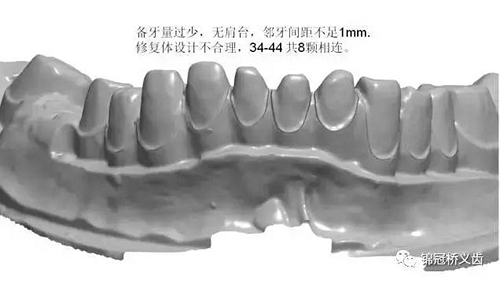

1、臨床備牙不合理或基牙條件不適合做氧化鋯

如:無(wú)肩臺(tái)、凹面肩臺(tái)、邊緣線不清晰、雙重邊緣線、備牙空間不足、基牙有倒凹或牙橋沒(méi)有共同就位道、基牙切端或頜緣過(guò)于尖銳等等。